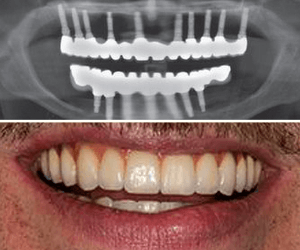

Implants